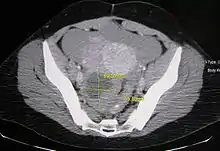

![]() | |

| A simple ovarian cyst of most likely follicular origin | |